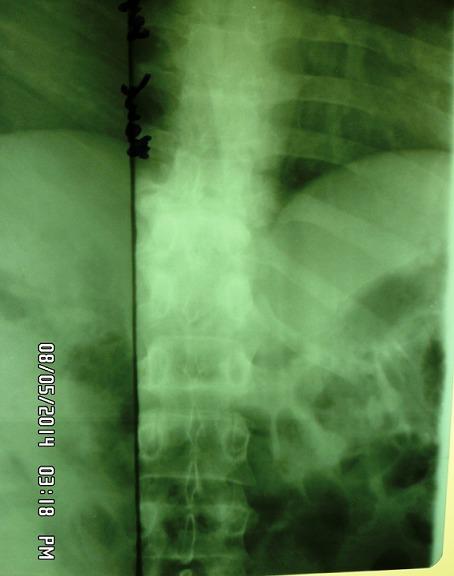

[腰背部寒性脓肿提示脊柱结核]

[Dorsolumbar cold abscess revealing Pott's disease].

Tuberculous cold abscesses are a rare and unusual form of extrapulmonary tuberculosis. We here report the case of a 27-year old patient with a 5-month history of left dorsolumbar swelling presenting with dorsolumbar cold abscess revealing Pott's disease without neurological complications. Examination of pus sample collected at the time the abscess was incised and drained helped to confirm the diagnosis of cold abscesses of TB origin. The patient underwent 12 months of anti-tuberculosis treatment which lead to a faster recovery; the sequelae was slight gibbosity.

摘要

结核性寒性脓肿是一种罕见的肺外结核形式。我们在此报告一例27岁患者,有5个月的左腰背部肿胀病史,表现为腰背部寒性脓肿,诊断为脊柱结核,无神经并发症。对脓肿切开引流时采集的脓液样本进行检查,有助于确诊结核源性寒性脓肿。该患者接受了12个月的抗结核治疗,恢复较快;后遗症为轻度脊柱后凸。